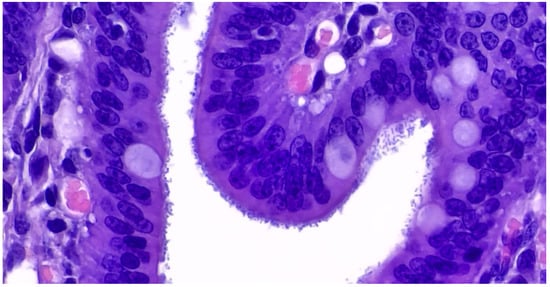

The microscopic lesions of PE are very characteristic and generally pathognomonic (Figure 23) and include:

(1)

hyperplasia of crypt enterocytes with the formation of elongated, dilated and dysplastic crypts;

(2)

increased mitoses;

(3)

reduction in, or complete loss of, goblet cells.

Figure 23. Ileum of pig affected by PE shows a hyperplastic epithelium of crypts (Haematoxylin and Eosin stain; 40×).